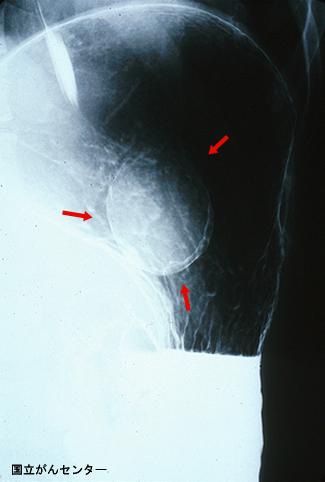

질환(병리주체)의 분류 양성 비상피성종양/낭포

부위(장기별) 위(부위)/분문

검사방법 X-P

종양의 최대경(밀리미터) 40이상